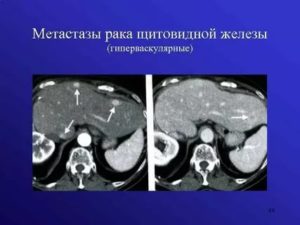

Метастазирование

Метастазы являются вторичным очагом злокачественной опухоли любой этиологии и локализации. Метастазирование в печень свидетельствует о раке:

- желудка;

- поджелудочной железы;

- молочных желез;

- легких.

Как правило, метастазы появляются на поверхности левой доли печени, так как именно этот участок располагается максимально близко к поджелудочной железе.

Метастазные образования поражают печень, если развивается опухоль молочной железы, мочеполовой системы, желудка, органов брюшной полости и легких.